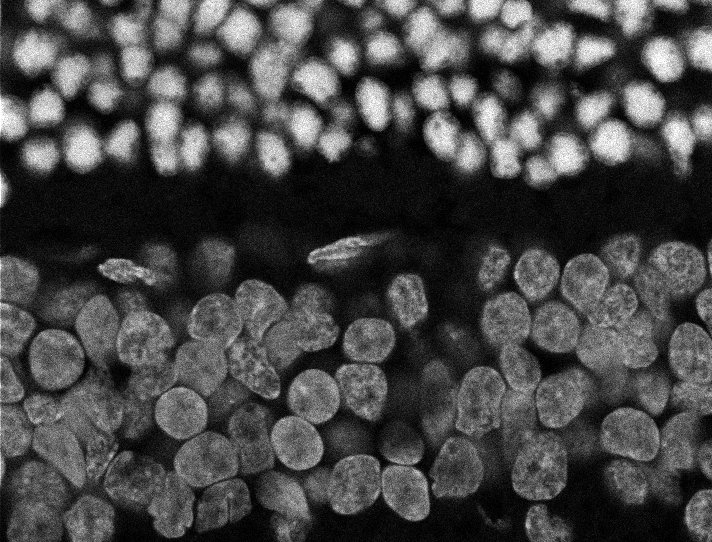

Overview 1

Actin

Nuclei

Nuclei - Bis

Tubulin